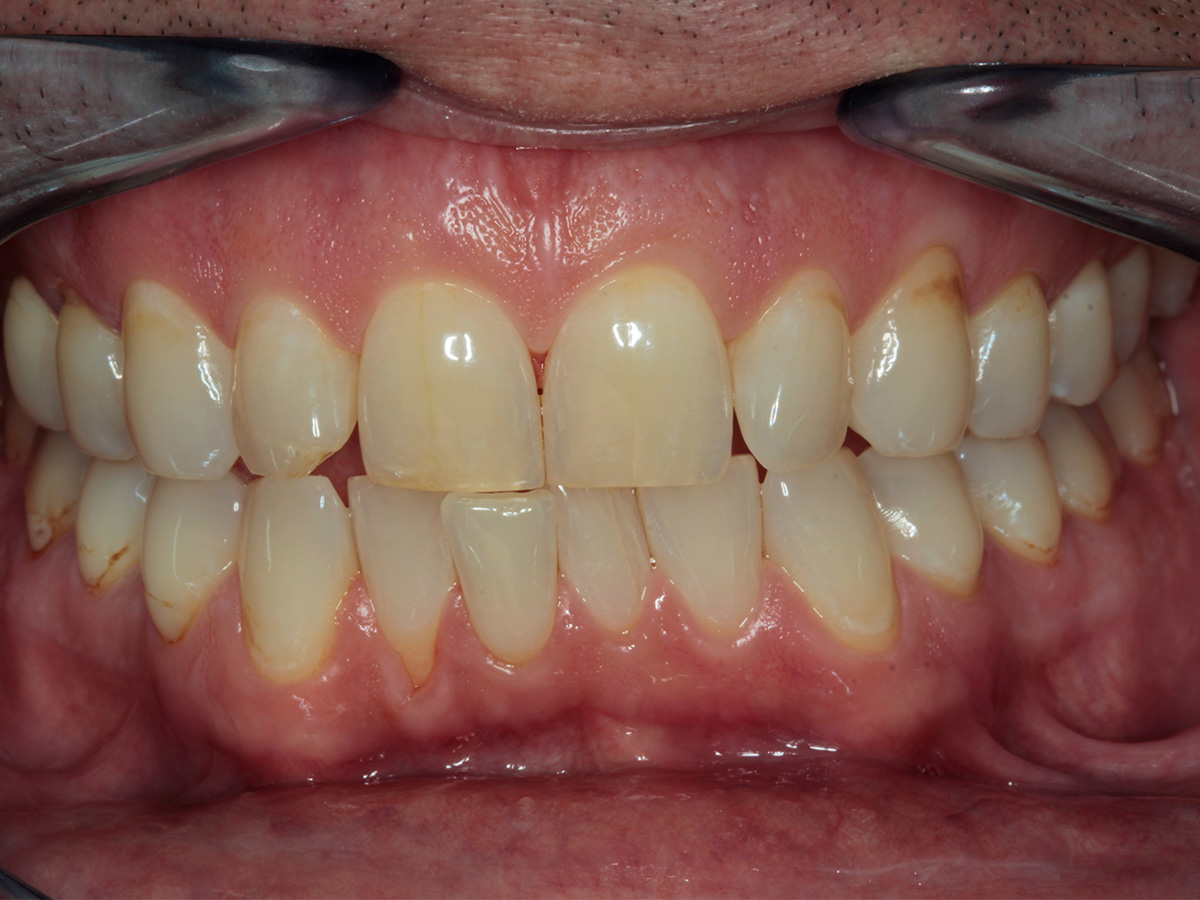

• Parodontale Krankheitsbilder erkennen